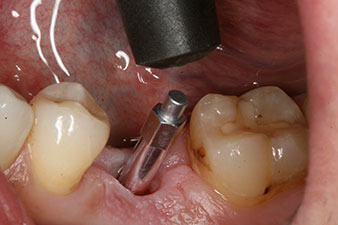

The torque used for the machine-driven placement was 43 Ncm. In addition, after screwing a measuring post (SmartPeg) specially matched to the implant, the ISQ value was measured with the probe of the W&H Osstell ISQ module.

This module is an optional extra for the W&H Implantmed and is docked to the implantology motor (see Fig. 11). The dimensionless ISQ value immediately after insertion was 64 orovestibular and 68 mesiodistal (maximum value = 100).

After healing of the soft tissue, the implant stability was measured again before delivery of the prosthetic restoration.

Both values were virtually unchanged and were between the medium and the high range – where the lower value is always used as the reference value that determines the treatment.

Therefore, successful osseointegration and adequate biological stability could be recorded, which enabled an impression to be taken in the same session.